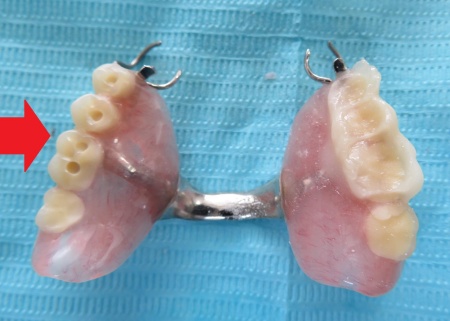

まず、入れ歯を装着した状態で噛み合う面に1mm程度、即時重合レジンと呼ばれる歯科用プラスチックを盛り、実際に噛んでいただきながら適切な噛み合わせの位置を慎重に確認して記録します。

即時重合レジンは、粉と液を混ぜると数分で硬化する性質がある材料です。

左側にレジンを盛り、噛み合わせを記録しました。